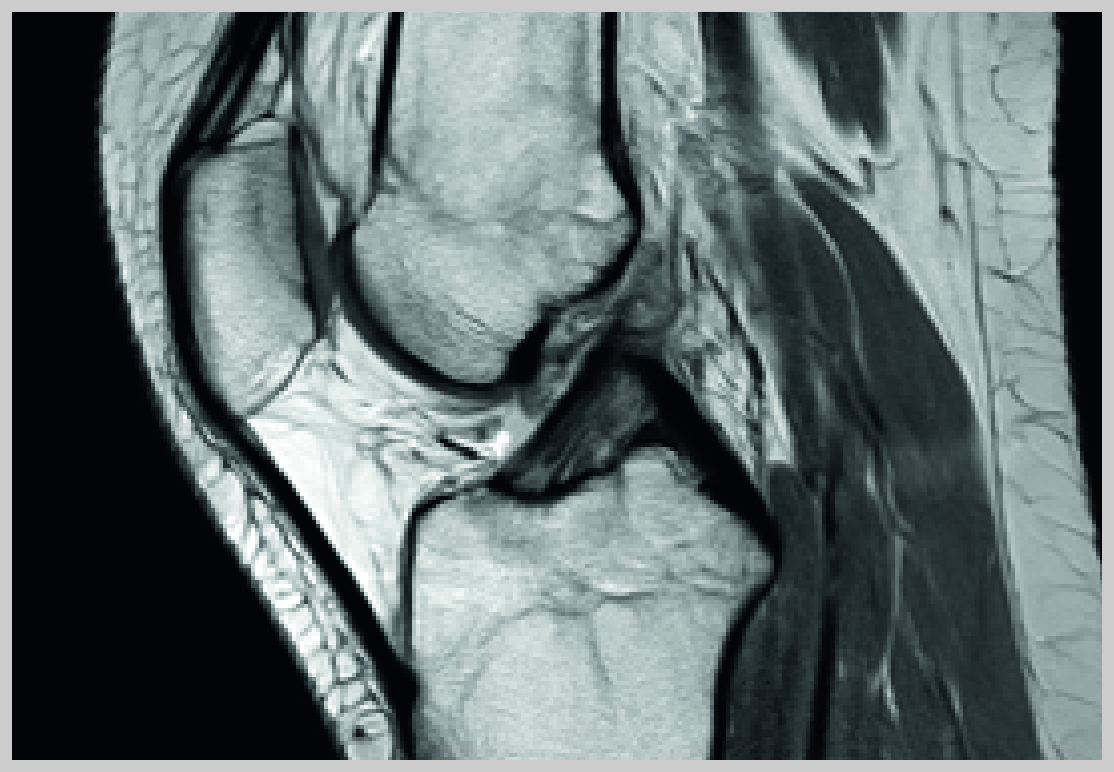

In vielen Fällen  wird dabei der Meniskus und /oder der Knorpel, aber auch die komplizierten Bandstrukturen des Kniegelenks in Mitleidenschaft gezogen.

Die Behandlungsbreite reicht von nicht-operativen Verfahren wie physikalische Therapie, Hilfsmittel (spezielle Bandagen, Schienen), Medikamente, Bestrahlung und  Injektionen bis hin zu Operationen wie Arthroskopische Chirurgie (Knorpel, Meniskus, Bandplastiken) oder im fortgeschrittenen Fall bis hin zur Versorgung mit einem künstlichen Gelenk.